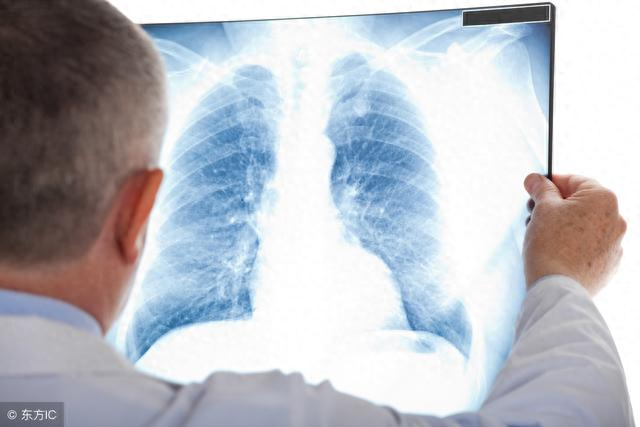

一、年龄。除了吸烟以外,年龄也是肺癌发病攀升的一个重要因素,根据研究显示,超过45岁就进入了肺癌的高发年龄。